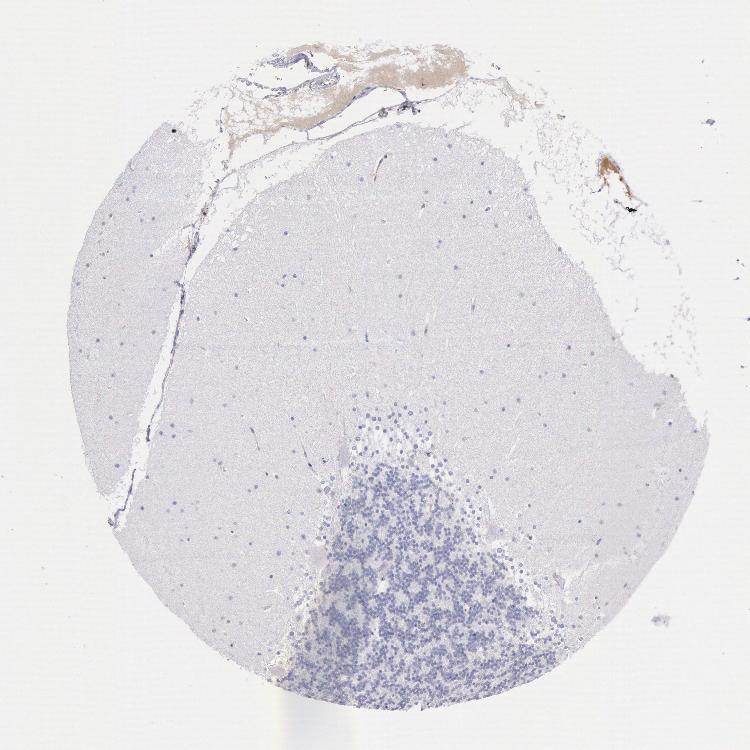

CEREBELLUM - Antibody stainingi

Antibody staining in the annotated cell types in the current human tissue is reported as not detected, low, medium, or high, based on conventional immunohistochemistry profiling in selected tissues. This score is based on the combination of the staining intensity and fraction of stained cells.

Each image is clickable and will lead to virtual microscopy that enables deeper exploration of all samples and also displays staining intensity scores, fraction scores and subcellular localization as well as patient and tissue information for each sample.

Antibody HPA000685Antibody HPA001295Antibody CAB016760

Purkinje cells Not detectedNot detectedNot detected

Cells in granular layer Not detectedNot detectedNot detected

Cells in molecular layer Not detectedNot detectedNot detected